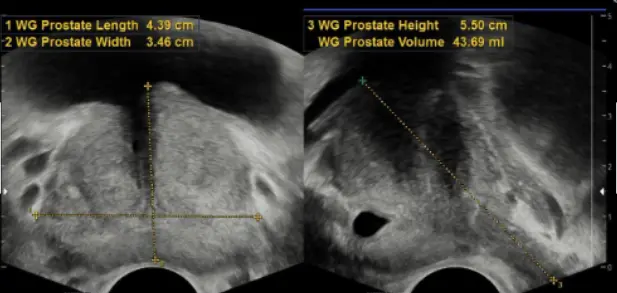

전립선비대증 치료에 있어 리줌 수술의 효과를 잘 보여줍니다.

천안 굿모닝비뇨기과는 기존의 전통적인 수술방법(경요도적 전립 선절제술;TURP, 광선택적 전립선기화술;KTP PVP, 전립선 홀뮴레이저 수술;HoLEP 등) 뿐만 아니라 리줌(REZUM), 전립선 결찰술(Urolift), 프로게이터(Pro-Gator)등 을 포함한 최소 침습적 수술방법도 가능하여 환자분의 상태와 상황에 맞춘 맞춤형 치료를 진행할 수 있습니다.